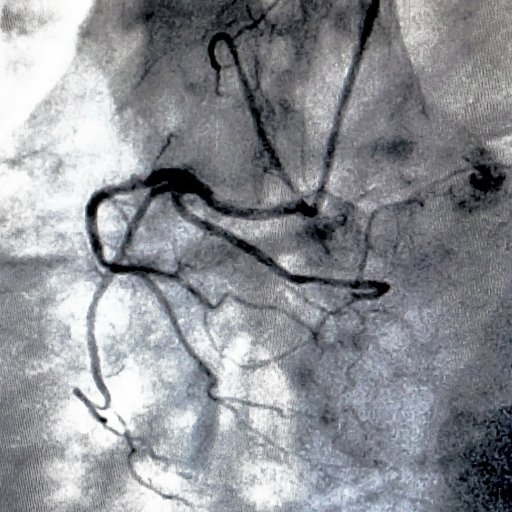

Es un estudio diagnóstico que permite visualizar las arterias mediante el uso de un medio de contraste y técnicas de imagen. Se utiliza para identificar estrechamientos, obstrucciones o alteraciones en los vasos sanguíneos, especialmente en las arterias coronarias, facilitando el diagnóstico preciso de enfermedades cardiovasculares y la planificación del tratamiento más adecuado.

Es un procedimiento diagnóstico y, en algunos casos terapéutico, que permite estudiar el funcionamiento del corazón y de las arterias coronarias mediante la introducción de un catéter delgado a través de un vaso sanguíneo. Este estudio ayuda a detectar obstrucciones, medir presiones dentro del corazón y evaluar el flujo sanguíneo, facilitando el diagnóstico y el tratamiento de diversas enfermedades cardiovasculares.